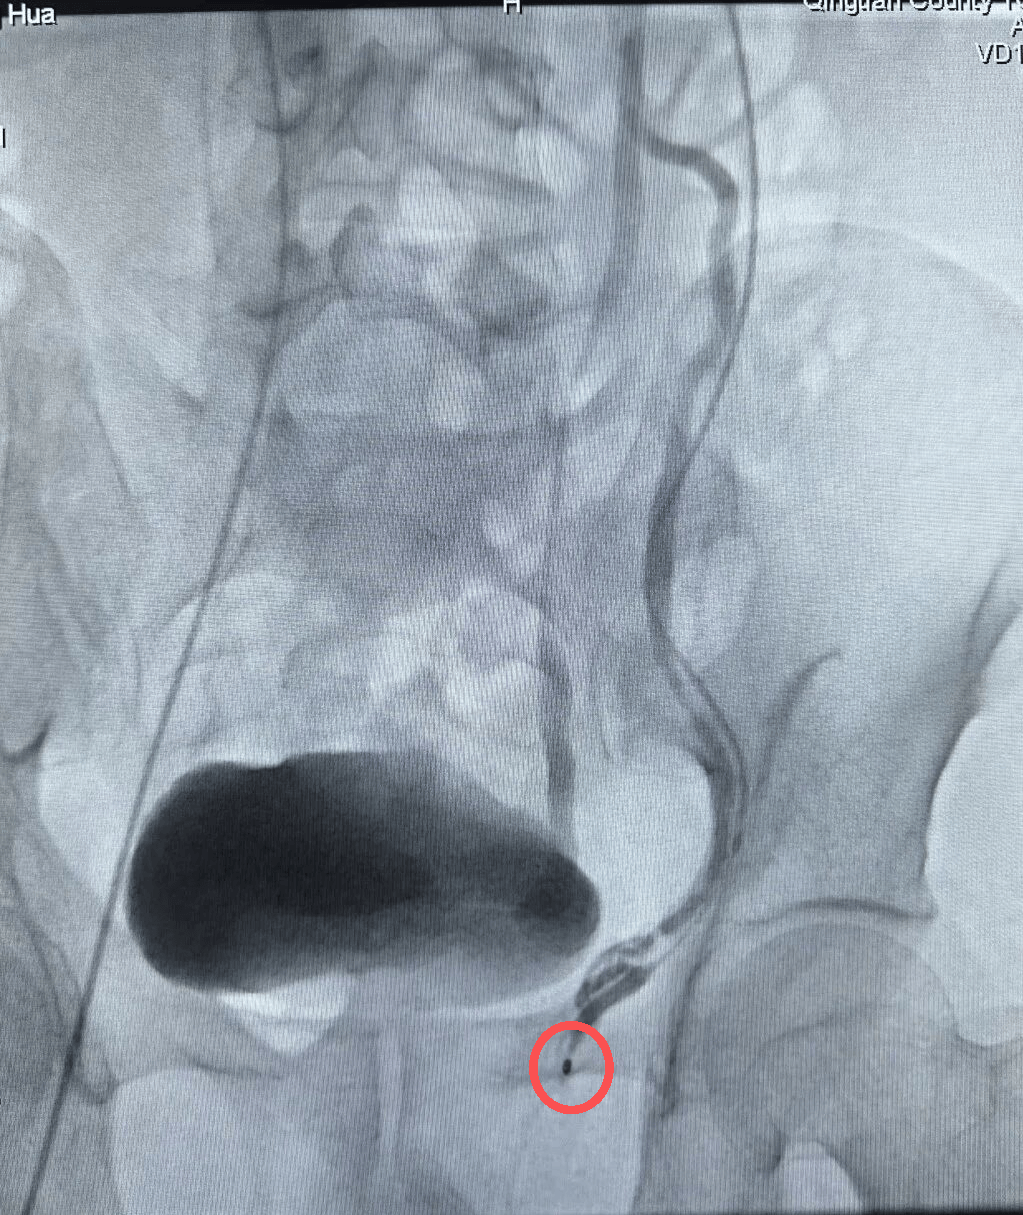

高嵩医生结合患者的生育需求、病情严重程度等综合情况,量身制定个性化介入栓塞治疗方案,在局部麻醉下为患者精准完成血管穿刺、造影定位、栓塞封堵等一系列操作。

精索静脉栓塞造影图

整个手术耗时短,患者全程无明显不适。术后当天患者即可下床活动,次日便顺利出院,微创诊疗的优势尽显。术后复查显示,患者阴囊坠胀症状明显缓解,为后续精液质量改善、实现生育目标奠定了坚实基础。